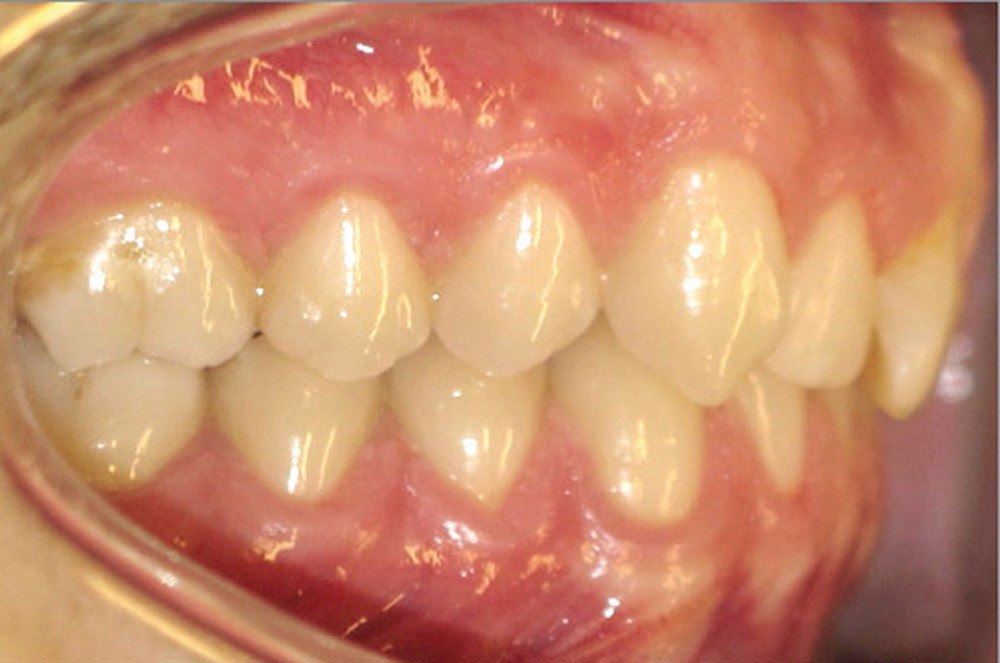

Examen endobuccal (fig. 2a-e)

L’arcade maxillaire est asymétrique, en hémi-lyre droite. Elle présente une mésio-position du secteur 1 en lien avec un encombrement antérieur estimé à 4 mm, se traduisant par une palato-position de la 12 et une rotation de la 11. On observe également des mésio-rotations des premières molaires et une palato-version incisive. L’arcade mandibulaire est ellipsoïde et présente un léger encombrement incisif (1 mm).

Concernant les relations occlusales, on observe une classe II complète subdivision droite. Le surplomb est absent et le recouvrement augmenté, estimé à 4 mm, a provoqué une usure des bords libres de 11 et 21 par attrition. Dans la dimension transversale, on constate une endoalvéolie maxillaire, ainsi qu’une concordance des médianes incisives entre elles, mais toutes deux déviées à droite par rapport au plan sagittal médian.